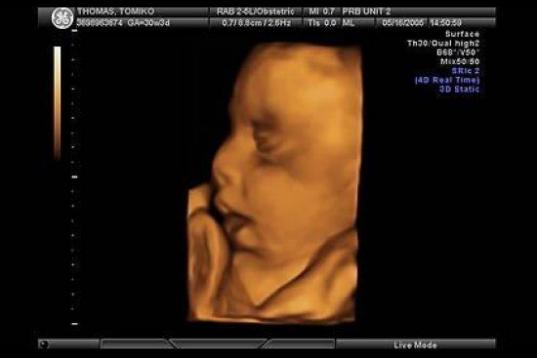

En esta galería puedes ver en fotos como es el desarrollo de un feto de semana en semana:

Desarrollo del feto, en fotos